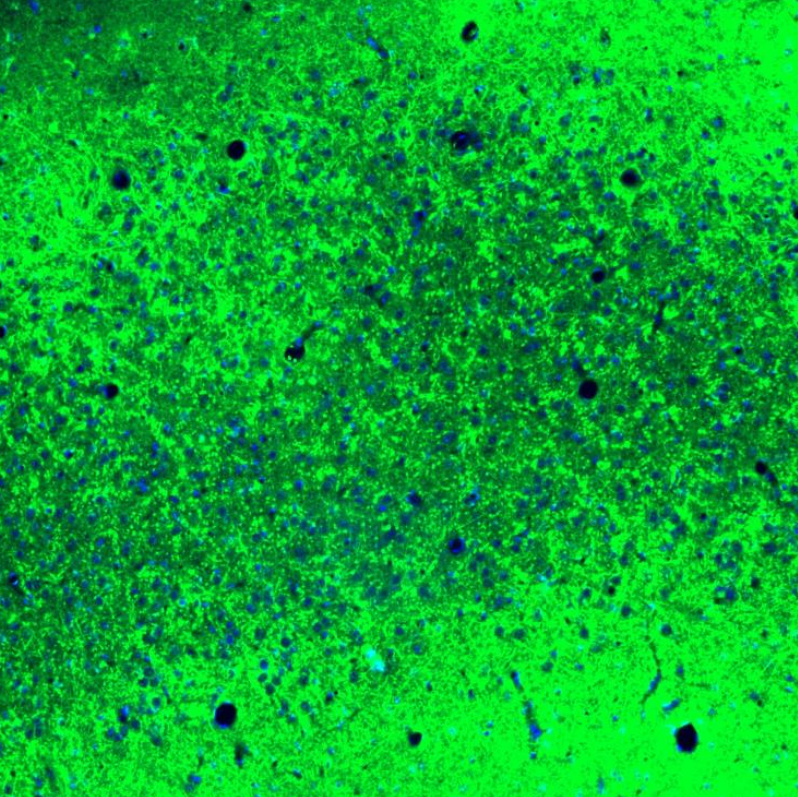

Immunofluorescence staining of mouse brain cortex shows strong cytoplasmic positivity in neuropil.